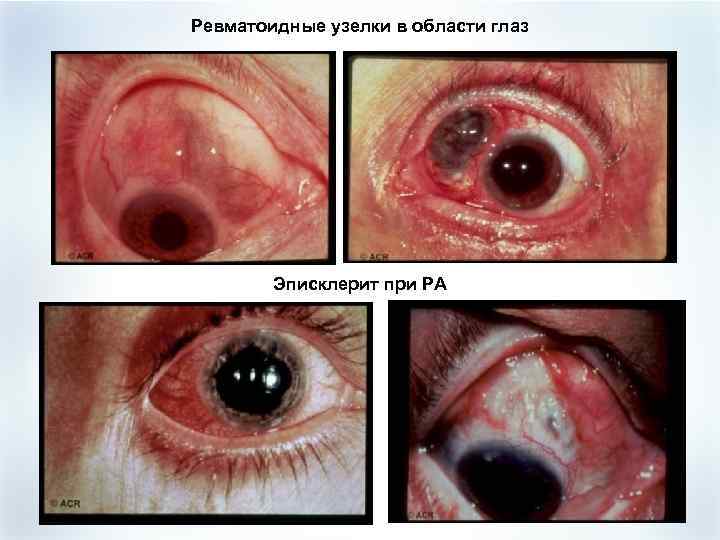

Поражение глаз при РА (редко) § § § Эписклерит Ирит Кератоконьюнктивит (при синдроме Шегрена) Осложнение – склеромаляция, прободение роговицы, энуклеация

Поражение глаз при РА (редко) § § § Эписклерит Ирит Кератоконьюнктивит (при синдроме Шегрена) Осложнение – склеромаляция, прободение роговицы, энуклеация

Ревматоидные узелки в области глаз Эписклерит при РА

Ревматоидные узелки в области глаз Эписклерит при РА